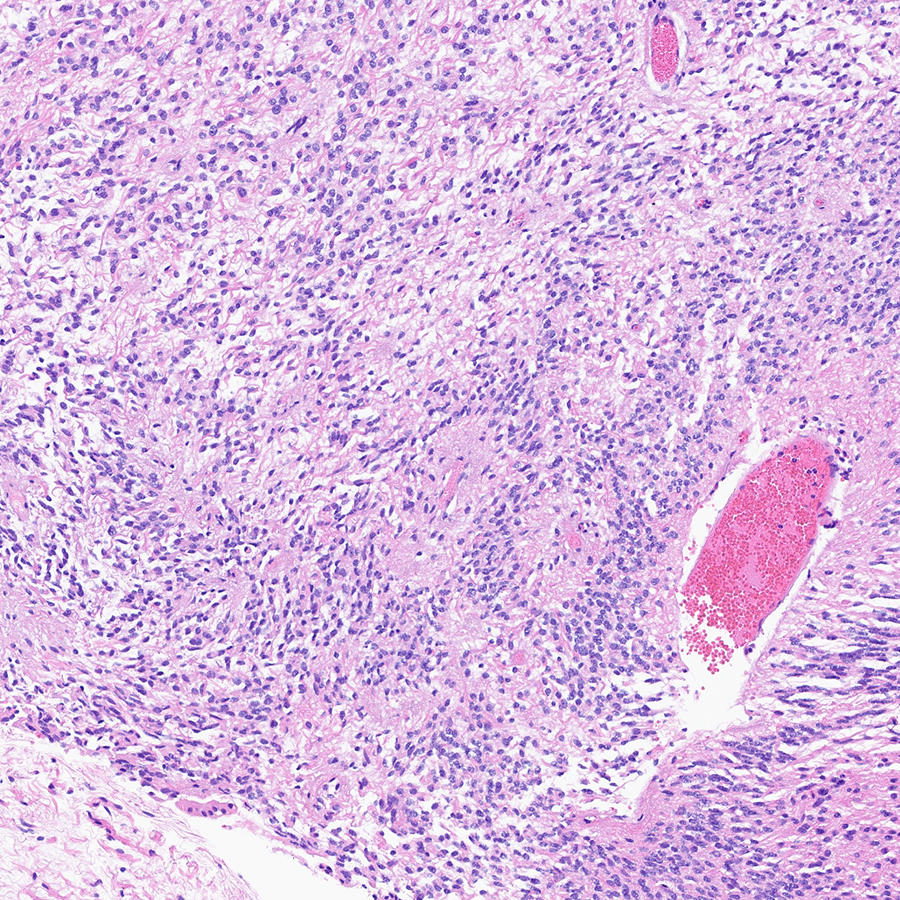

Our recently published manuscript in Cancer Cell – Diffuse hemispheric glioma, H3G34R/V-mutant (H3G34-DHG) - cell.com/cancer-cell/fu…